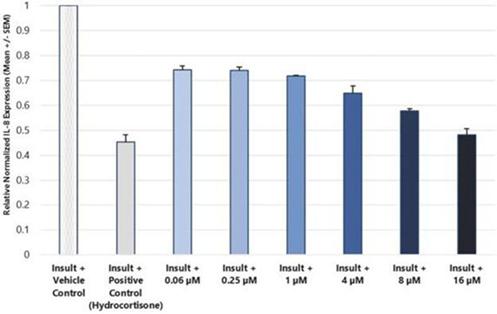

In addition to relief of symptoms, inflammation, pain, and others, we believe INM-755 may impact the underlying disease by enhancing skin integrity in a subset of EB patients. We have completed more than 30 preclinical pharmacology and toxicology studies to investigate the effects of CBN. Several of these nonclinical studies explored the effect on important symptoms such as pain and inflammation. In in vitro pharmacology studies, CBN demonstrated activity in reducing markers of inflammation. CBN upregulated expression of a type of keratin called keratin 15, or “K15”, which might lead to skin strengthening and reduced blister formation in EB simplex, or “EBS”, patients with mutations in another keratin called keratin 14, or “K14”. The anti-inflammatory activity of CBN may be beneficial in healing chronic wounds caused by prolonged inflammation. Following a review of our toxicology studies, the Netherlands National Competent Authority and Ethics Committee approved the initiation of a Phase I clinical study in healthy volunteers. We have safety data with INM-755 cream in 22 healthy adult volunteers from our first Phase I study (755-101-HV) in which subjects had the INM-755 cream applied to their upper backs daily for 14 days. An interim safety analysis of the first 16 subjects was reviewed by the Netherlands National Competent Authority and Ethics Committee and determined to be adequate to allow initiation of the second Phase I study testing INM-755 cream on small wounds. That second study has completed and we now have safety data for INM-755 cream applied to small open wounds daily for 14 days in 8 healthy adult volunteers.

In preclinical pharmacology studies, CBN demonstrated activity as an anti-inflammatory and antinociceptive agent. CBN upregulated expression of keratin 15 (K15), which might lead to skin strengthening and reduced blister formation in EBS patients with keratin 14 (K14) mutations. At the cream concentrations chosen for clinical development, it does not appear to impede wound healing of partial-thickness wounds. Its anti-inflammatory activity may be beneficial in healing chronic wounds caused by prolonged inflammation.